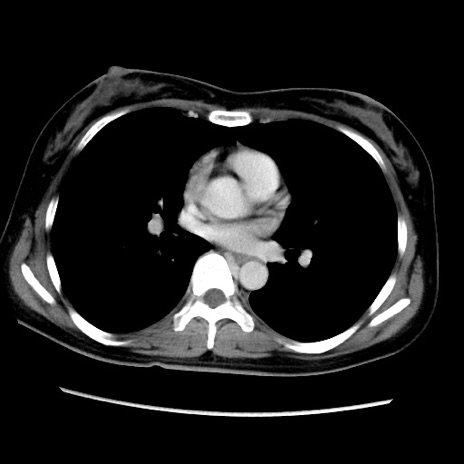

症例39(横断像)

【症例】40歳代女性

【主訴】上下腹部痛

【現病歴】2日目から下腹部痛あり。夜間は痛みで眠れなかった。昨日より上腹部痛と下痢が出現。臥位で痛みは軽快したため、休んでいた。本日になって臥位でも立位でも痛みが強くなってきたため救急要請。

【既往歴】子宮内膜症

【身体所見】部:平坦・軟、左上下腹部に圧痛あり、反跳痛あり。

【データ】WBC 21800、CRP 26.78